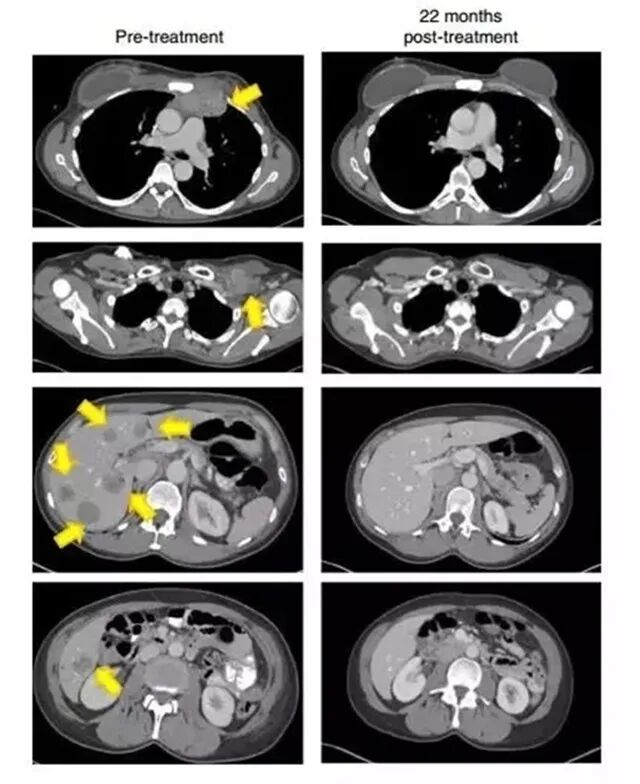

四个月后,朱迪接受了900亿个有特异性杀伤能力免疫细胞的输注,一周过后,她感觉自己的身体起了明显的变化,比如胸部的肿瘤感觉逐渐缩小。又过了一两周,胸腔内的肿瘤完全消失了。

22个月后,影像检查显示(黄色箭头)肿瘤消失得无影无踪

该结果对于癌症治疗领域而言,是一个历史性的突破。因为Judy Perkins已经是终末期癌症病人,相当于被传统疗法宣告了“死刑”,而细胞免疫疗法让她迎来了新生。